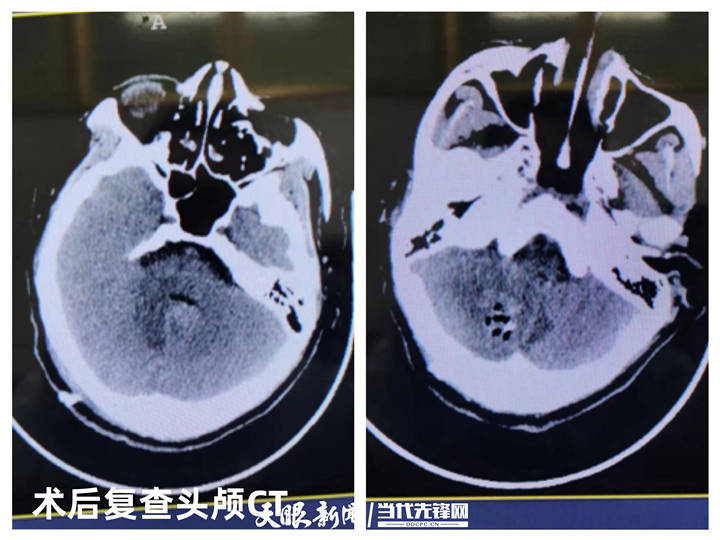

清水县人民医院外三科行开颅血肿清除手术成功救治一名急性重型颅脑

开颅血肿清除术(脑出血开颅血肿清除)